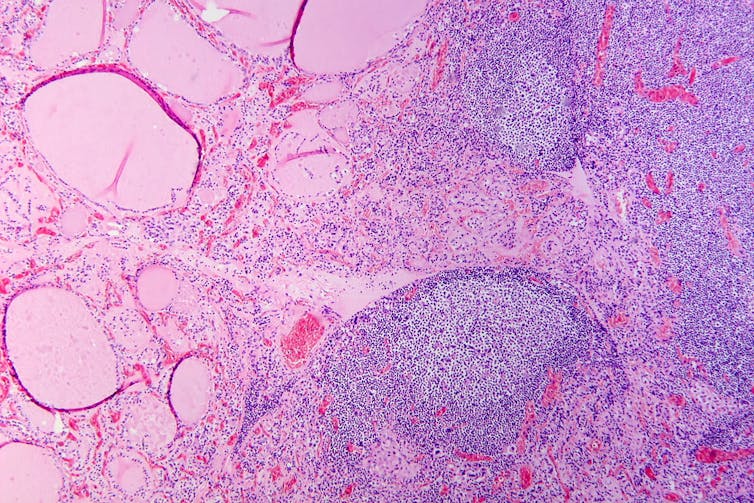

Hashimoto’s thyroid disease, named after the Japanese doctor who discovered it in 1912, is also known as Hashimoto’s thyroiditis or chronic lymphocytic thyroiditis. The disease can cause the immune system to mistakenly produce proteins called antibodies (thyroid peroxidase and thyroglobulin). These can cause inflammation and long-term damage to the thyroid gland. Over time, as thyroid tissue is inflamed and/or destroyed, there can be a decrease in the production of thyroid hormones (hypothyroidism).

The disease has also been linked with an increased risk (but low incidence) of the lymphocytes of the thyroid turning into cancer cells to cause thyroid lymphoma.